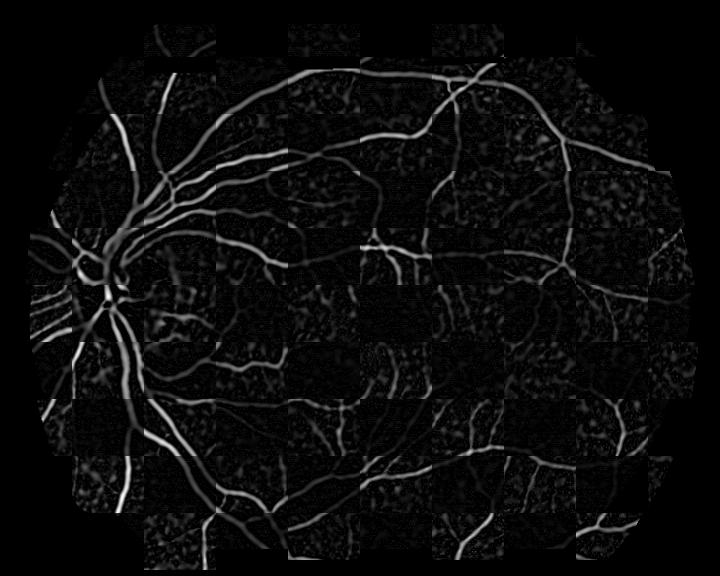

The obtained vessel tree is fragmented at some points. Discontinuities appear at crossovers and bifurcations where vessels with different directions meet, and in the middle of a single vessel due to illumination and contrast variations of the image. Bifurcation and crossover detection is approached by joining the segmented vessels as described in [16]. Bifurcations are established where an extended segment under a given maximum distance intersects another segment. Crossovers, instead, are considered as nearby double bifurcations. They are detected at positions where two bifurcations are closer than a given distance and the relative angle between their directions is below a certain threshold. Figure. 1 shows an example of a retinography/angiography pair and the result of the identified vessel tree and landmarks.

Refer to caption

Figure 1: Example of multimodal image pair and the results of the landmark detection method: (a) input retinography; (b) input angiography; (c)(d) resulting binary vessel trees along with the detected landmarks for (c) the retinography and (d) the angiography.